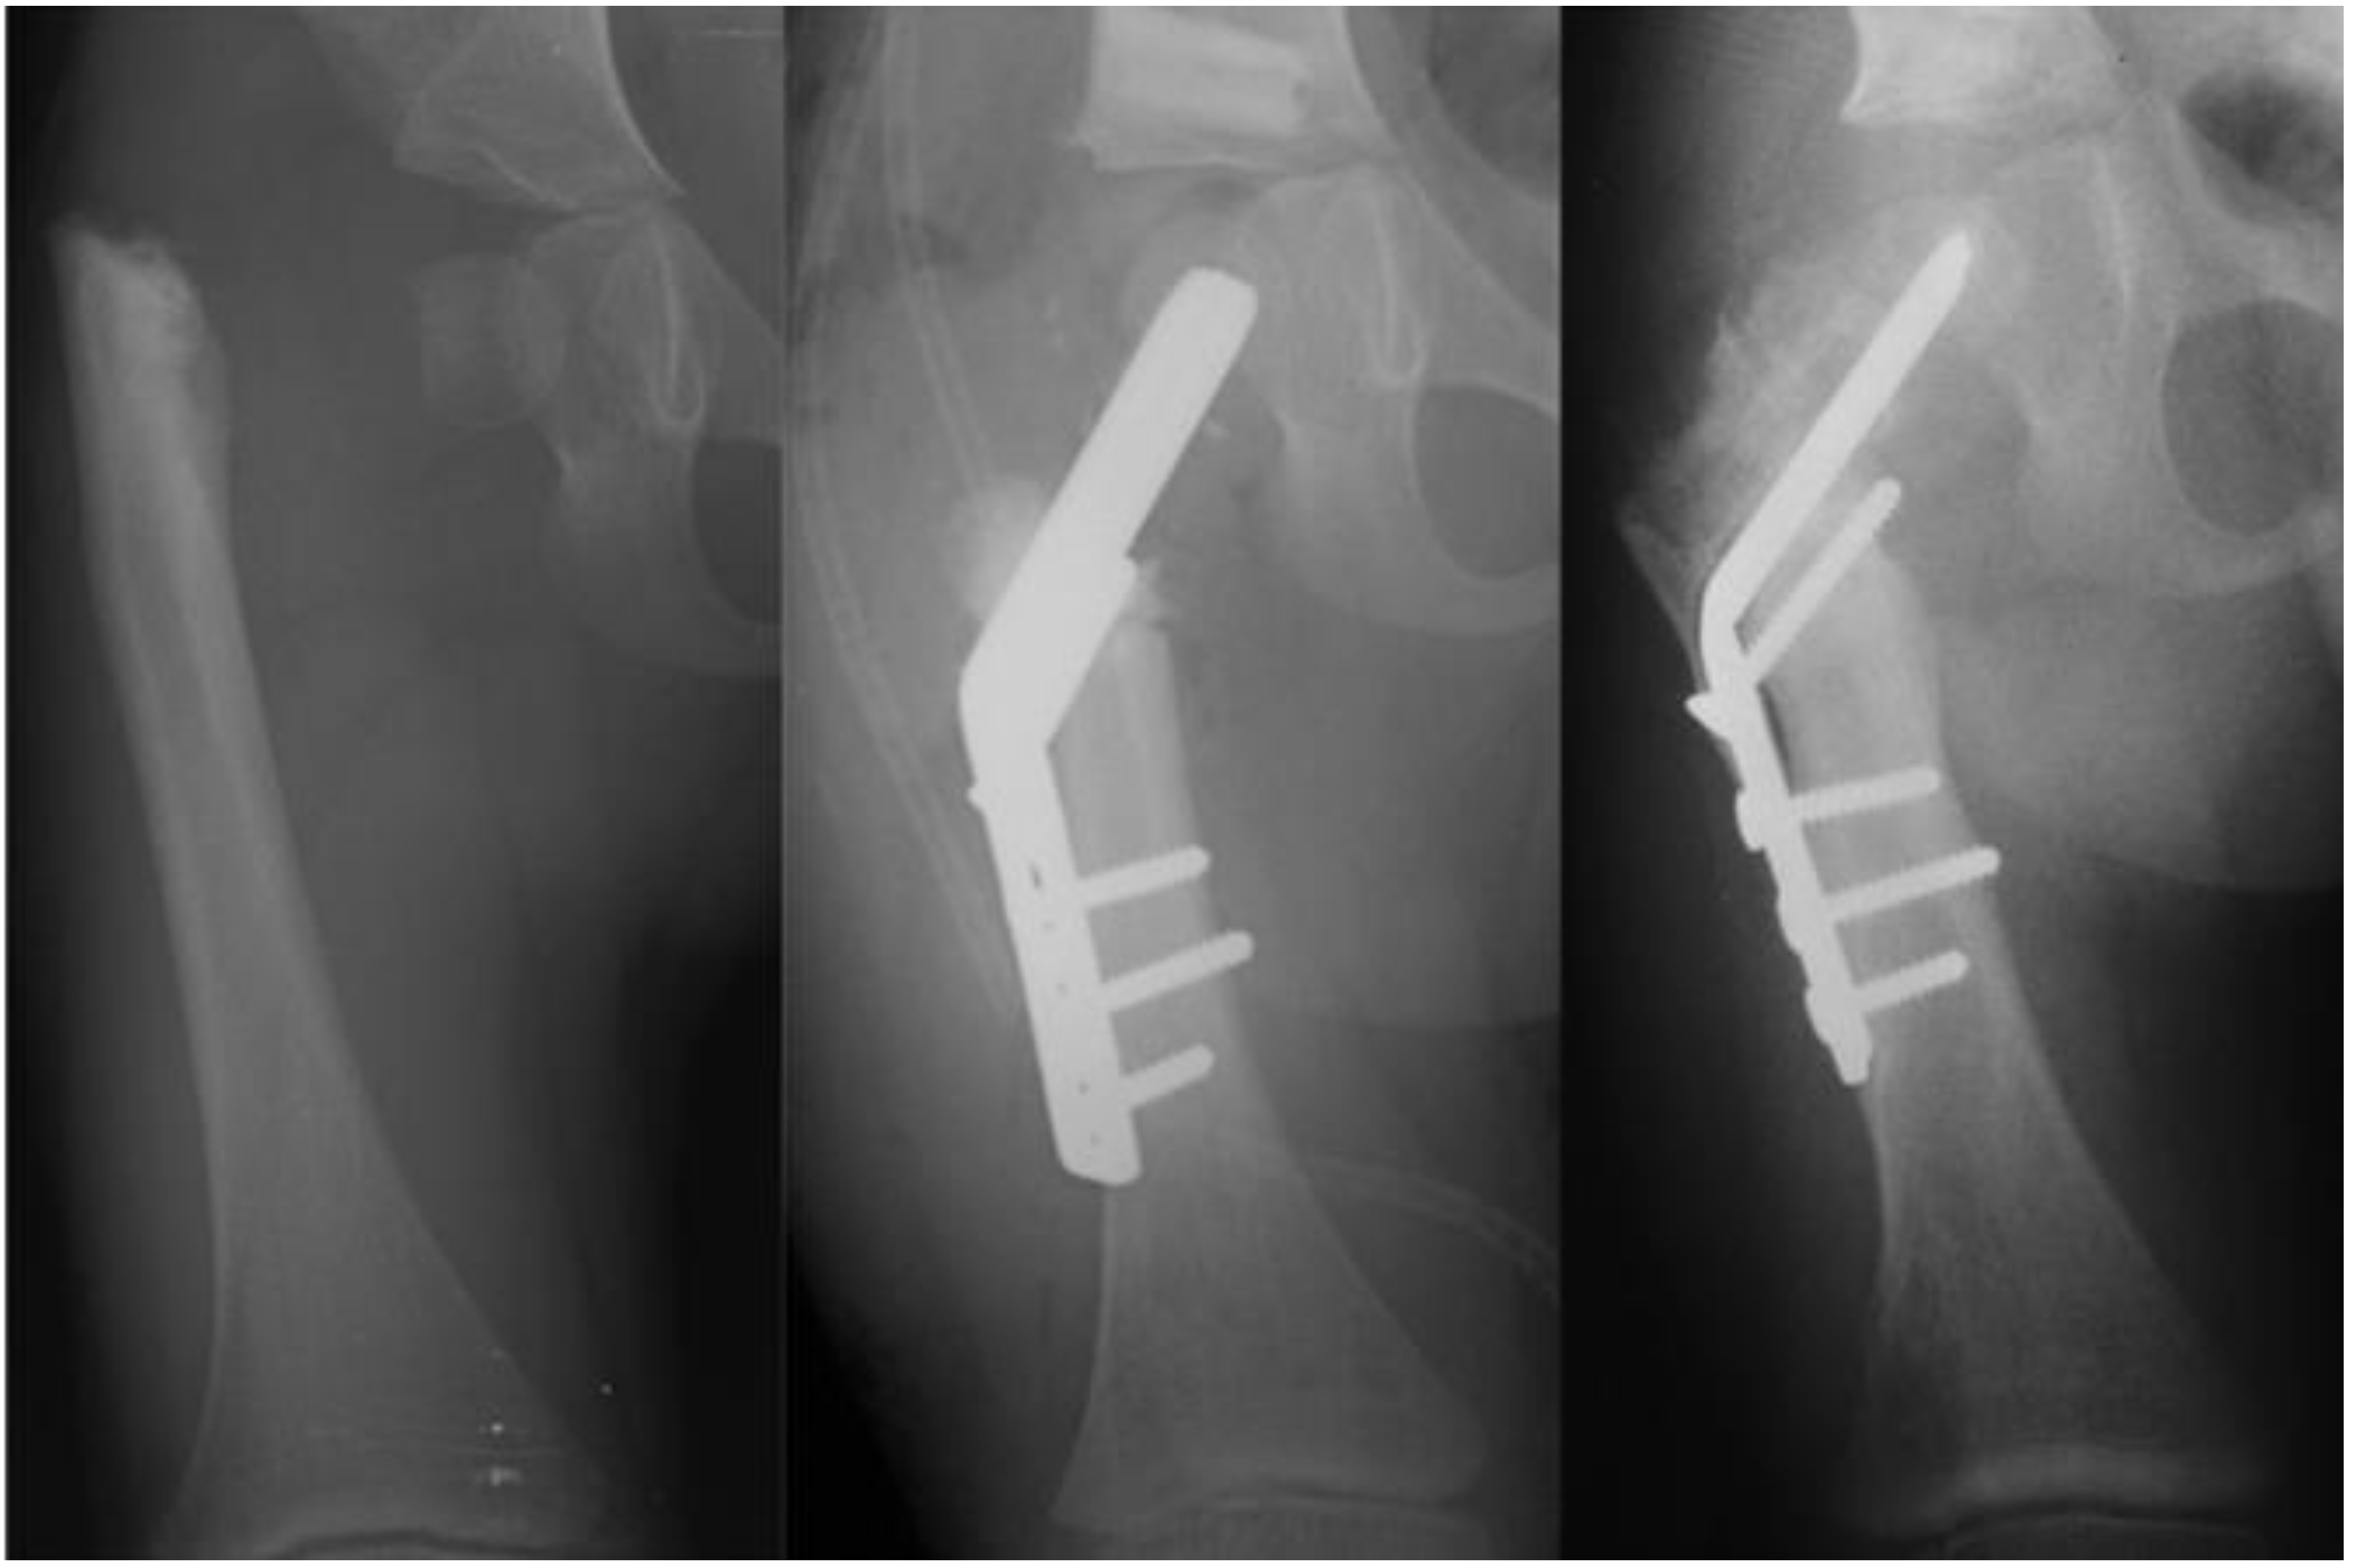

Late complications, such as recurrent varus deformity and delayed ossification of the femoral neck, were reported in the earliest versions of the SH surgery [7,8]. In order to address the recurrent varus, the non-fixed angle fixation (Rush rod and tension band wire) was replaced with a much stronger fixed angle construct; a sliding hip screw (SHS) (Smith and Nephew, Memphis, TN, USA) or a 130 degree cannulated blade plate (Smith and Nephew, Memphis, TN, USA) [7,8] (Figure 4).

Figure 4. Illustration after SUPERhip procedure using a fixed angle device for fixation; sliding hip screw with additional rotation control second screw (left), and blade plate (right). Note on the right side there is a drill hole made for insertion of BMP2 superior to the blade.